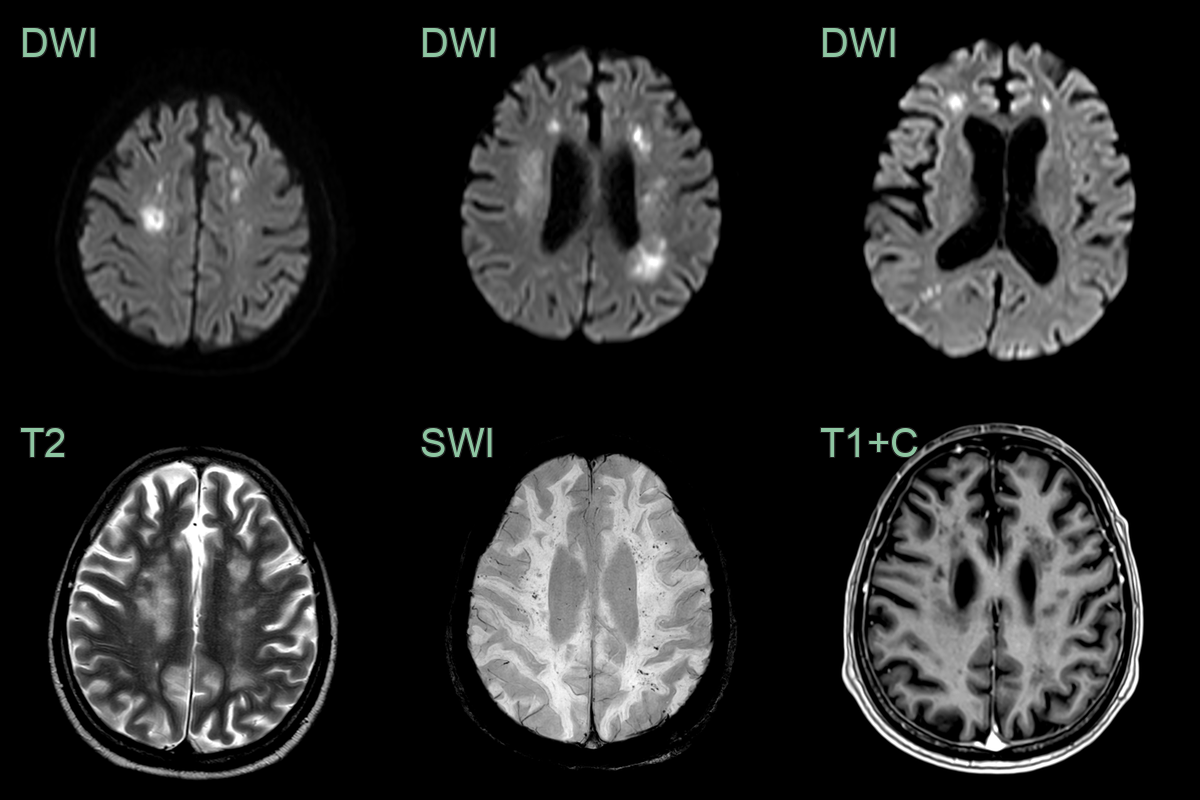

• A 50-year-old patient presented with headache and dizziness.

• MRI showed hazy white matter hyperintensity, puntate diffusion restriction, microhemorrhages and perivascular enhancement.

• Intravascular lymphoma was identified following a non-targeted biopsy in the right frontal lobe.